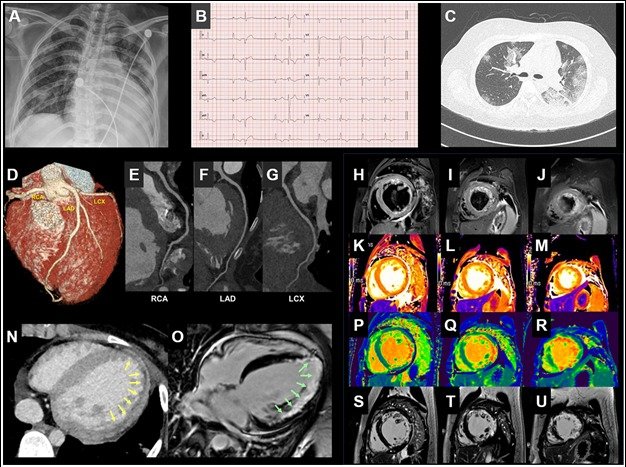

계명대 의과대학 연구진이 국내  신종 코로나바이러스 감염증(코로나19) 환자에서 처음으로 심장질환 발생을 확인했다. 각각 엑스레이,(A) , 심전도(B), 컴퓨터 단층촬영(CT) (CTC-G, N), 그리고 자기공명영상장치(MRI) 사진이다.  특히 사진 N과 사진 O는 심장에서 발생한 부종을 확인할 수 있다. © 뉴스1

연구팀은 여러 의료 영상 이미지를 통해 코로나19와 동반된 심근염을 확인했다고 밝혔다.

진단결과 흉부 방사선 사진은 폐와 심장 비대가 생겼음을 보여줬으며(사진A) 심전도 검사에서는 부정맥의 증상이 나타났다.(사진B)

흉부 컴퓨터단층촬영(CT)은 폐에서 간유리음영이 나타났으나 관상동맥은 정상이었다.(사진C-G) 또한 CT와 자기공명영상장치(MRI)를 통해 심장에 생긴 부종을 확인했다.(사진N-O)